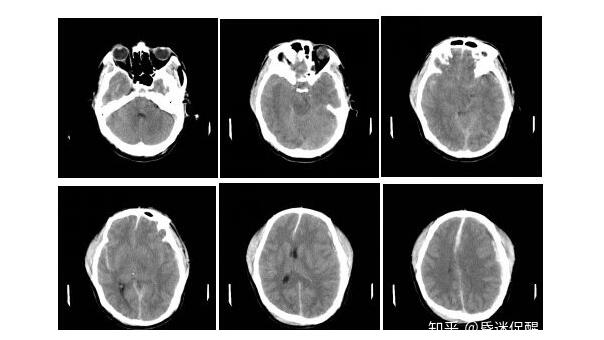

复查头颅CT提示:脑疝形成、左侧额颞顶硬膜下血肿增加、弥漫性轴索损伤。急诊送手术室行了“左侧额颞顶开颅、硬膜下血肿、脑膜成型、去骨瓣减压术”。

伤后2小时(2017-05-26 04:20)